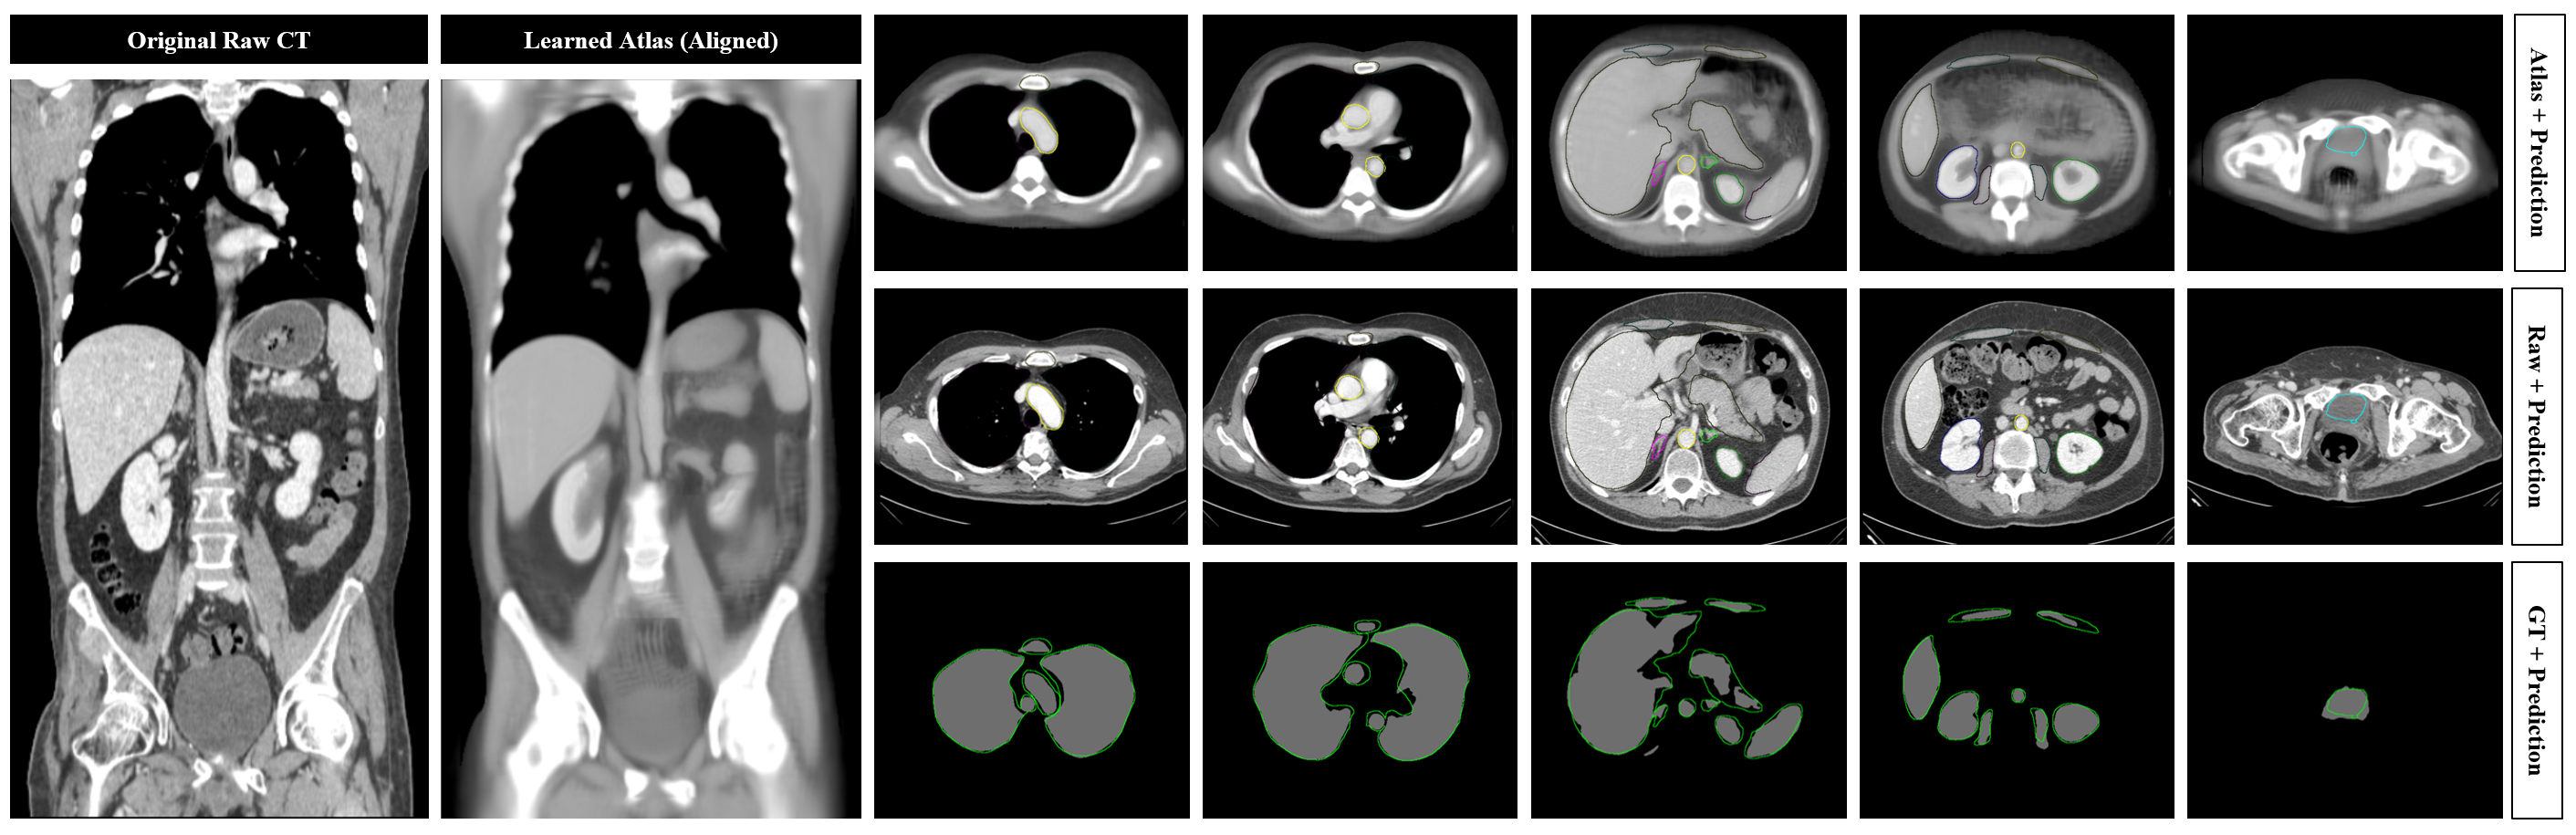

Refer to caption

Figure 5: One-Shot Segmentation (Anatomy3 Cohort). In this example, segmentation masks are shown for the lungs, trachea, sternum, thoracic aorta, abdominal aorta, liver, spleen, pancreas, kidneys, iliopsoas muscle, and bladder. See Figure 4 for further details.